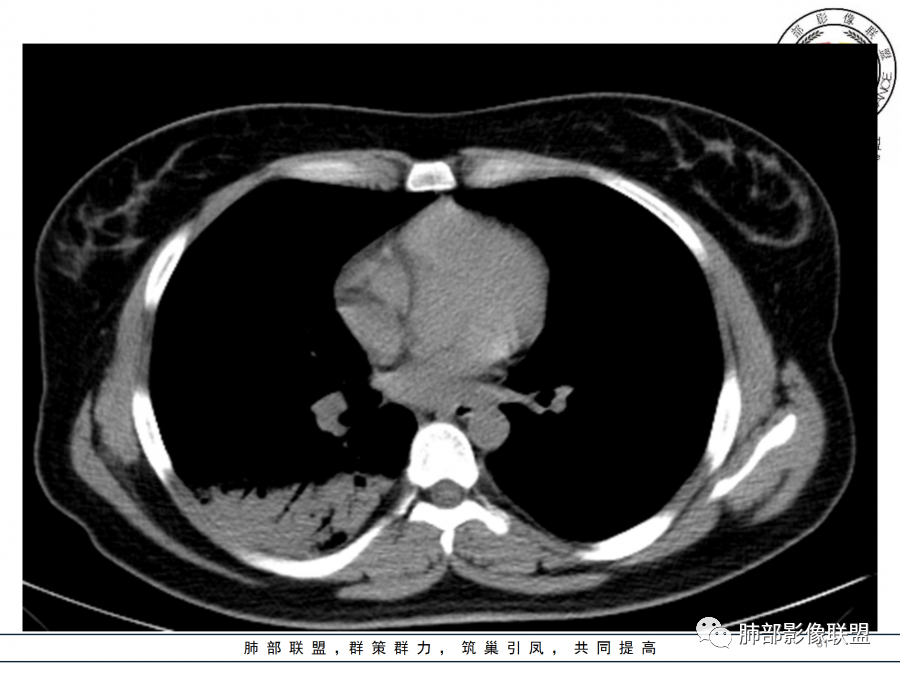

年轻女性,急性病史,发热,WBC17.42*10^9/L,NE%82.8%,

痰革兰染色示:G-杆菌1+、G+球菌1+,未检出真菌,抗酸染色阴性。

大片实变影

细菌性感染?隐球菌?结核?梗死?

淋巴瘤?肺炎型肺癌?支原体?病毒?

1.年轻女性,咳嗽、发热(38.8°),起病急,血象高。影像上大片实变影为主,一般会首先考虑细菌性肺炎,尤其是肺炎链球菌感染等。疗效不满意时考虑其他。

2.影像上怀疑其他病灶的理由有:

1)实变影为大小不等多中心性。

2)沿胸膜下分布趋势(不同于大叶性肺炎的肺叶“造型”)。

3)周围较大范围磨玻璃影及小叶间隔增厚。

4)病灶体积增大明显(叶间裂推移)。

3.腺病毒肺炎可以符合上述改变:实性密度,间质分布为主等。

4.隐球菌感染可以符合上述改变:胸膜下多中心实变密度为主,磨玻璃晕等。但隐球菌临床症状大多隐匿、迁延,影像变化缓慢。

5.本例患者血象高,影像渗出明显,尚不能排除混合感染可能。